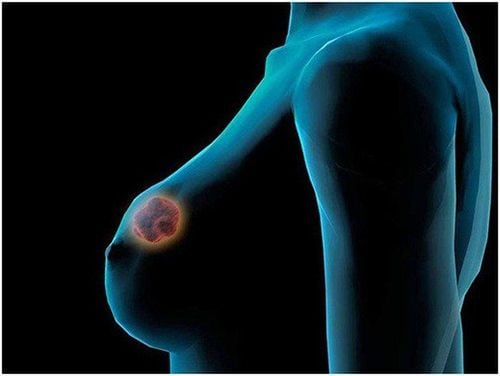

Ung thư vú bộ ba âm tính là ung thư có thụ thể estrogen, progesterone và HER2 âm tính.

Điều này nghĩa là sự phát triển của ung thư không được thúc đẩy bởi hormone estrogen và progesterone, hoặc bởi protein HER2. Vì vậy, ung thư vú bộ ba âm tính không đáp ứng với thuốc điều trị nội tiết tố hoặc thuốc nhắm vào thụ thể protein HER2, mà được điều trị thành công bằng các loại thuốc khác.

1. Ung thư vú bộ ba âm tính là gì?

- Ung thư vú bộ ba âm tính được coi là ác tính và tiên lượng kém hơn so với các loại ung thư vú khác, do có ít loại thuốc điều trị. Ung thư vú bộ ba âm tính có nhiều khả năng di căn ra ngoài vú và tái phát sau khi điều trị.

- Ung thư vú bộ ba âm tính thường có cấp độ cao hơn các loại ung thư vú khác. Cấp càng cao, các tế bào ung thư càng ít giống với tế bào vú khỏe mạnh bình thường về hình dạng và mô hình phát triển. Trên thang điểm từ 1 đến 3, ung thư vú bộ ba âm tính thường ở cấp độ 3.

- Ung thư vú bộ ba âm tính thường giống với nhóm basal like, nghĩa là giống như các tế bào cơ bản nối với ống dẫn vú. Nhóm basal like thường có xu hướng tiến triển nhanh hơn và độ ác tính hơn - như ung thư vú bộ ba âm tính. Không phải tất cả các bệnh ung thư vú thuộc nhóm basal like đều là ung thư vú bộ ba âm tính.